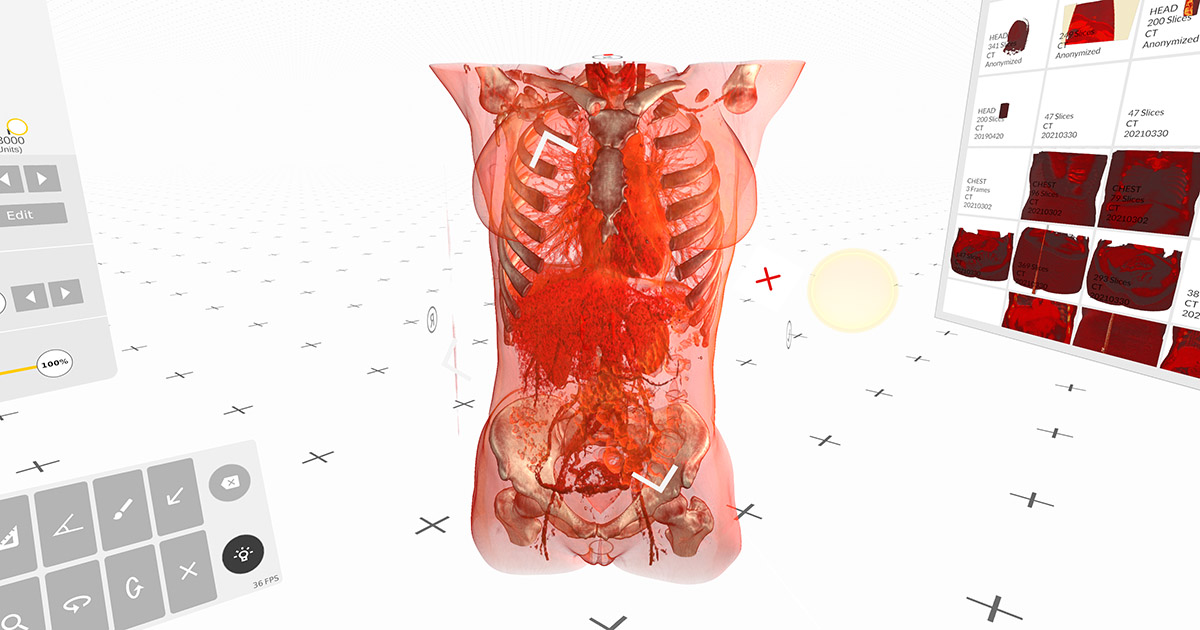

Animated medical imaging plays an important role in thoracic and cardiac surgery. Medicalholodeck now allows the import of animated, 4D medical imaging from CT, MRI, and echocardiography. Used in virtual reality, 4D data adds significant value to surgical planning, training, and education.

Read more News